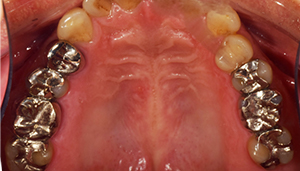

治療前:上の歯

治療前:下の歯

治療後:上の歯

担当医師所見:

左上第1大臼歯は抜歯し、仮歯に置き換えた後治癒を待ちジルコニアBrで補綴。また右上第1大臼歯は根管治療終了後にジルコニアクラウンで補綴。前歯部は審美性を考慮しジルコニアボンドにて補綴した。 色調、形態共に調和がとれている。

治療後:下の歯

下顎右側第1大臼歯は抜歯後、仮歯に置き換え治癒を待った後ジルコニアステイニングBrにて補綴。 全顎的に色調・形態共に調和がとれている。